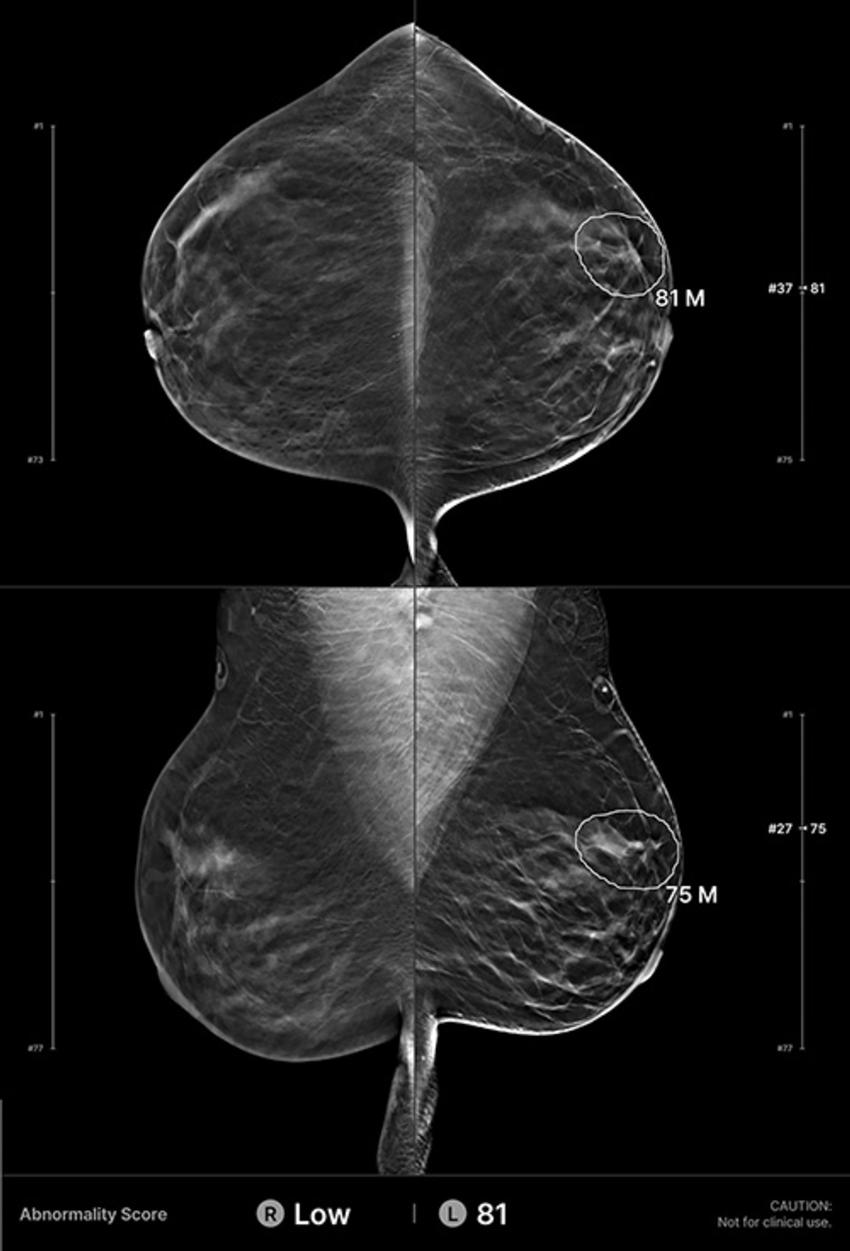

Figure 2. Example of an interval cancer retrospectively detected by the artificial intelligence (AI) algorithm. A 41-year-old woman presented for a screening digital breast tomosynthesis examination; its findings were interpreted as negative. Ten months later, the patient presented with a lump in the left breast and was subsequently diagnosed with grade 3 invasive ductal carcinoma. At retrospective evaluation of the initial screening mammogram, the AI algorithm marked a suspicious lesion (white outline) in the left breast, with high scores of 81 on the craniocaudal view and 75 on the mediolateral oblique view. This area of architectural distortion corresponds to the cancer that was subsequently diagnosed.